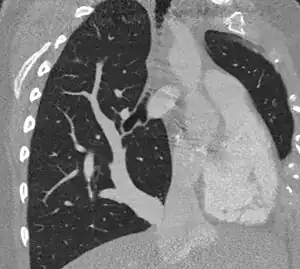

| Scimitar syndrome chest CT | |

Scimitar syndrome, or congenital pulmonary venolobar syndrome, is a rare congenital heart defect characterized by anomalous venous return from the right lung (to the systemic venous drainage, rather than directly to the left atrium).[1] This anomalous pulmonary venous return can be either partial (PAPVR) or total (TAPVR). The syndrome associated with PAPVR is more commonly known as Scimitar syndrome after the curvilinear pattern created on a chest radiograph by the pulmonary veins that drain to the inferior vena cava.[2] This radiographic density often has the shape of a scimitar, a type of curved sword.[2] The syndrome was first described by Catherine Neill in 1960.[3]